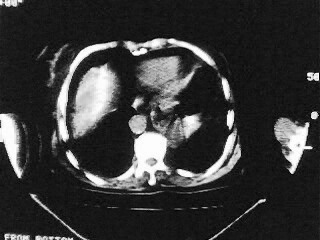

女,79,咳 嗽月余,无其它不适

后纵隔内左心房至肝左叶后方椎体中线偏左巨大软组织包块,其壁均匀比较薄,其内可见宽气液平。

考虑食管裂孔疝。建议钡餐检查